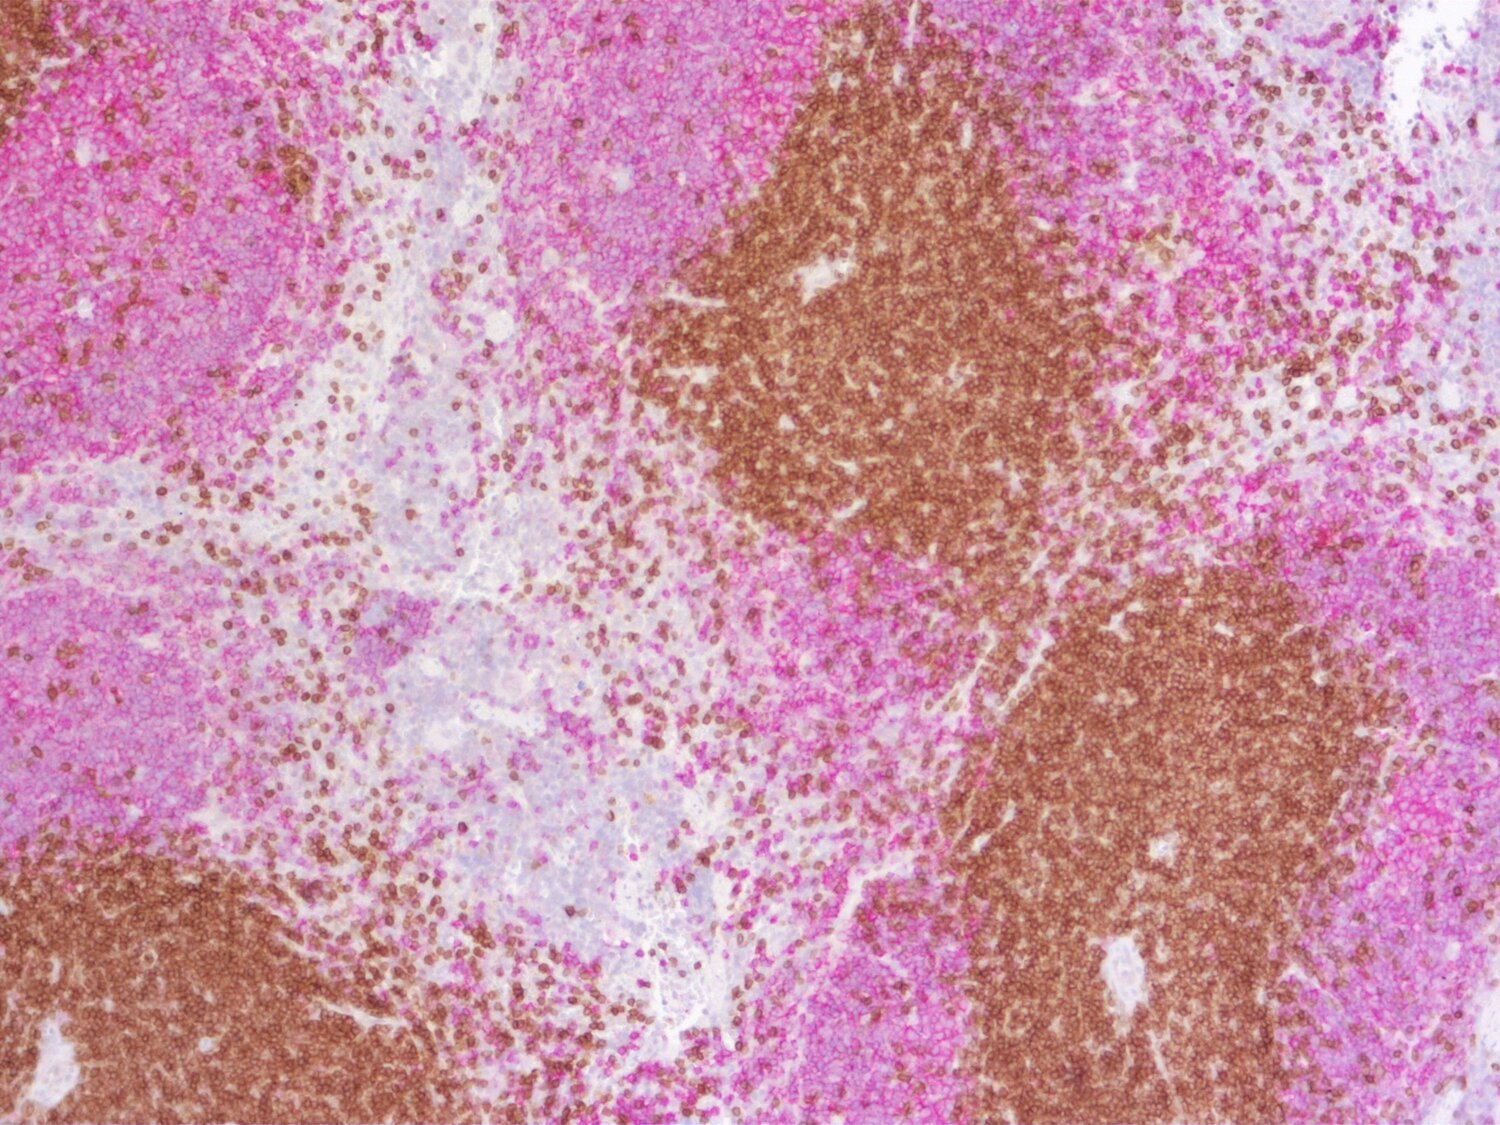

Indirect immunostaining of a formalin fixed paraffin-embedded mouse breast cancer model with rabbit anti-mouse CD19 (cat. no.: HS-439 003; DAB). Nuclei have been visualized by haematoxylin staining (blue).